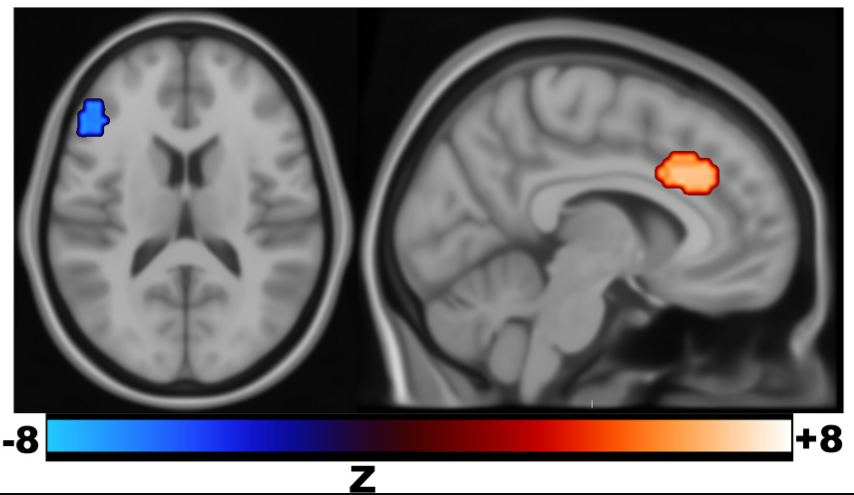

第一项试验的参与者基线时和治疗后的rs-fMRI数据对比确定了因SNT治疗而产生了显著时间结构变化的两个脑区,而假SNT对照组则没有相应变化,这两个脑区分别是SNT的刺激位置DLPFC和双侧ACC,左侧DLPFC相对其他脑区活动提前,而ACC相对其他脑区活动延迟。

左侧DLPFC(左)活动提前,ACC(右)活动延迟